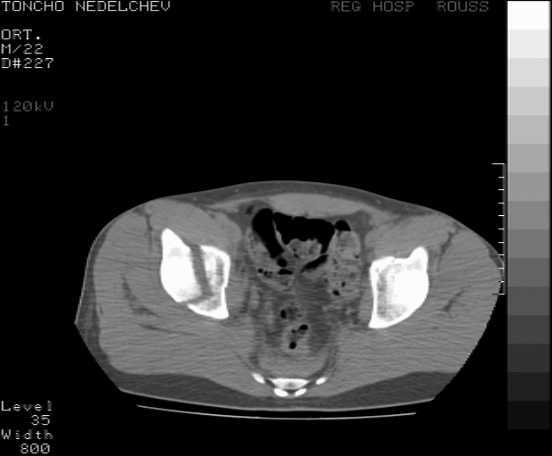

Here are some more axial images. What is your opinion as for the timing of the operative treatment?